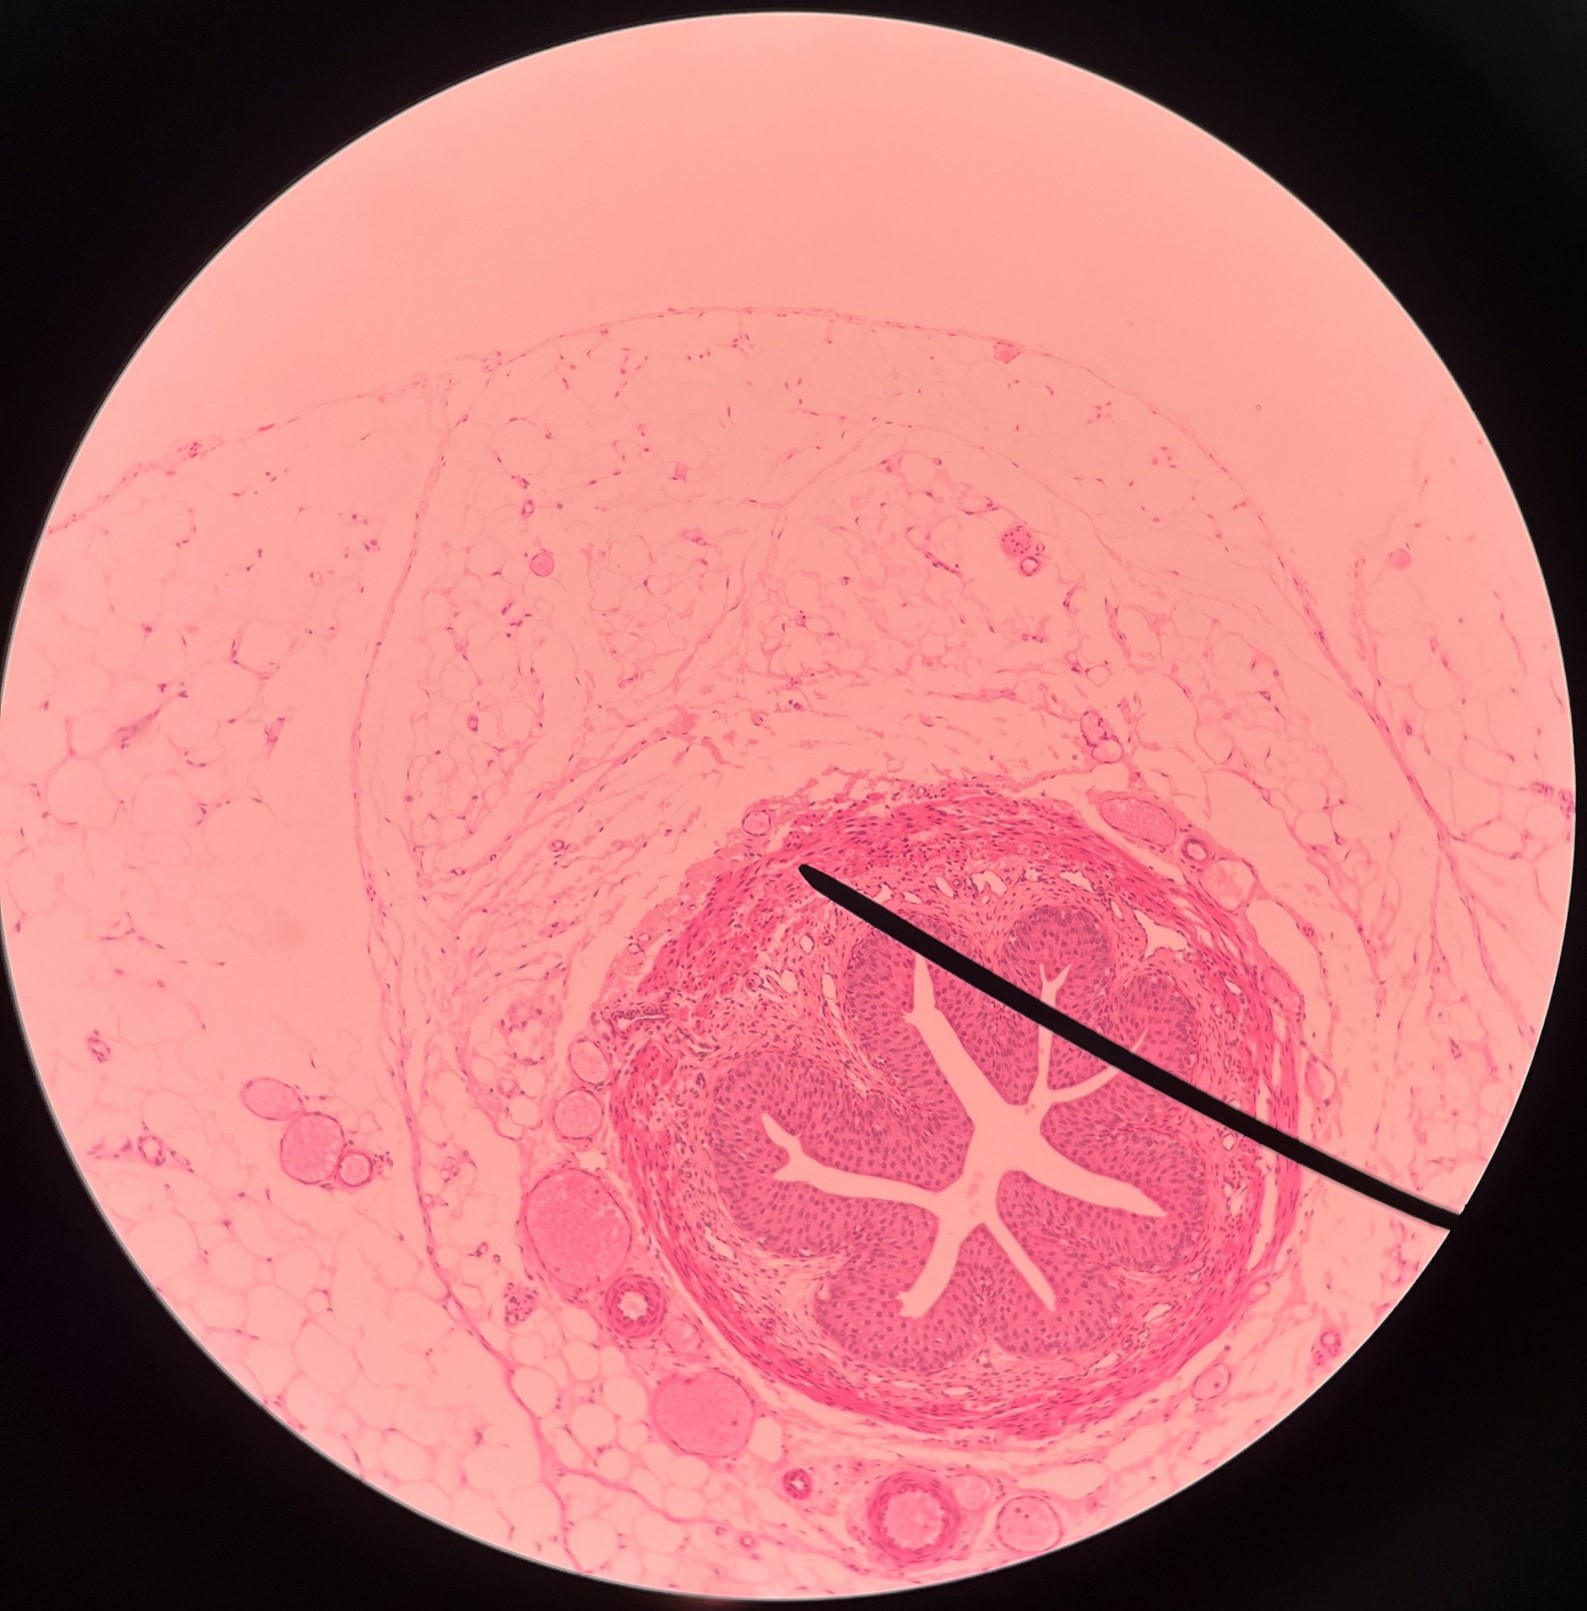

adventitia

• Slide histology of the ureter.

• The outermost layer of the ureter.

• Composed of connective tissue.

• Superficial to the circular layer of the muscularis.

circular layer of muscularis

• Slide histology of the ureter.

• A smooth muscle layer of the ureter.

• Superficial to the longitudinal layer of the muscularis and deep to the adventitia.

longitudinal layer of muscularis

• Slide histology of the ureter.

• A smooth muscle layer of the ureter.

• Superficial to the mucosa and deep to the circular layer of the muscularis.

mucosa

• Slide histology of the ureter.

• The innermost layer of the ureter.

• Composed of urothelium.

• Faces the lumen of the ureter and is deep to the longitudinal layer of the muscularis.